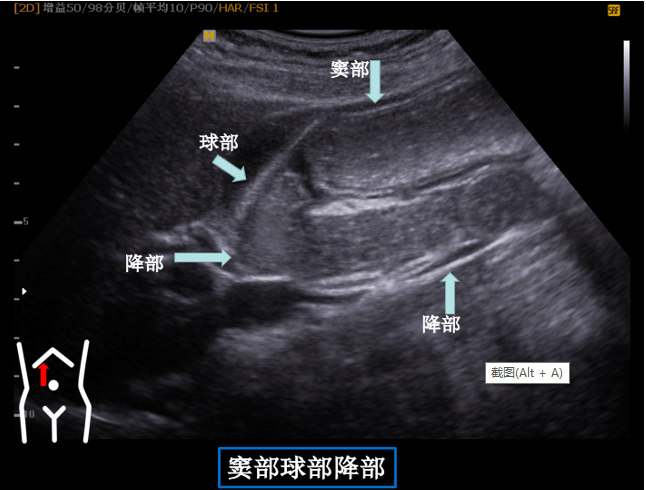

第四组胃窦球部切面

患者从右卧位改成平卧此时头也随着患者改变体位而由横切改为纵切在脐孔与右肋缘连线处扫出胃窦幽门管幽门孔球部降部水平部